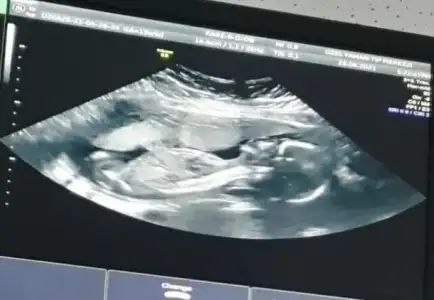

Merhaba lütfen tahmin yaparmısınız 2 yıl öncede yapmıştınız tutmuştu :)))

• 20210502_063913.webp

20210502_063913.webp

14,9 KB · Görüntüleme: 58